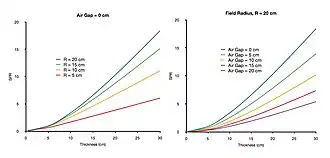

- The first three methods can be readily understood on the basis that the more absorber atoms that are presented to the incoming X-ray beam, the greater the likelihood of scattering events. This is illustrated in Figure 3.17.5 which shows the predictions of a broad-beam analytical model[9] of the SPR dependence on imaging geometry factors for different thickness of soft tissue which includes multiple-scattering events. It can be seen that the estimated SPR increases rapidly with increasing tissue thickness for increases in the field size and reductions in the size of the air gap between the patient and image receptor. The consequent subject contrast is therefore highly dependent on these factors. It can also be seen in the figure that the SPR is greater than 1 for most geometrical conditions - even for imaging just 5 cm of tissue. The intensity of scattered radiation can therefore be assumed to dominate the primary intensity for almost all radiographic examinations. Methods of scatter eduction can therefore greatly improve subject contrast. Note, however, that introducing an air gap can increase image magnification, and that reducing the field size through tight beam collimation is therefore the most applicable of these methods in many clinical imaging situations.